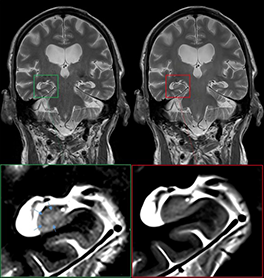

Coronal T2 images in an 89-year-old male patient undergoing MRI for suspected neurodegenerative disease.

Deep Resolve Boost in 2D MRI for Neuroradiology: A Comparative Evaluation of Diagnostic Gains and Potential Risks

Deep Resolve Boost applied to accelerated acquisition (DRB-ACC) offers the potential to reduce MRI acquisition time and improve image quality, but studies on its impact on artifacts, anatomical delineation, and imaging findings are scarce. In this study of 256 paired 2D sequences, DRB-ACC showed good or fair image quality in most cases and equivalent lesion depiction in 91.6% of cases. However, anatomical delineation was inferior in key regions, and artifacts were more pronounced or newly introduced in many sequences. DRB-ACC enables acceleration of 2D MRI while maintaining image quality, but caution is needed in scenarios requiring high anatomical detail.

Hakim et al., AJNR Am J Neuroradiol. 2025